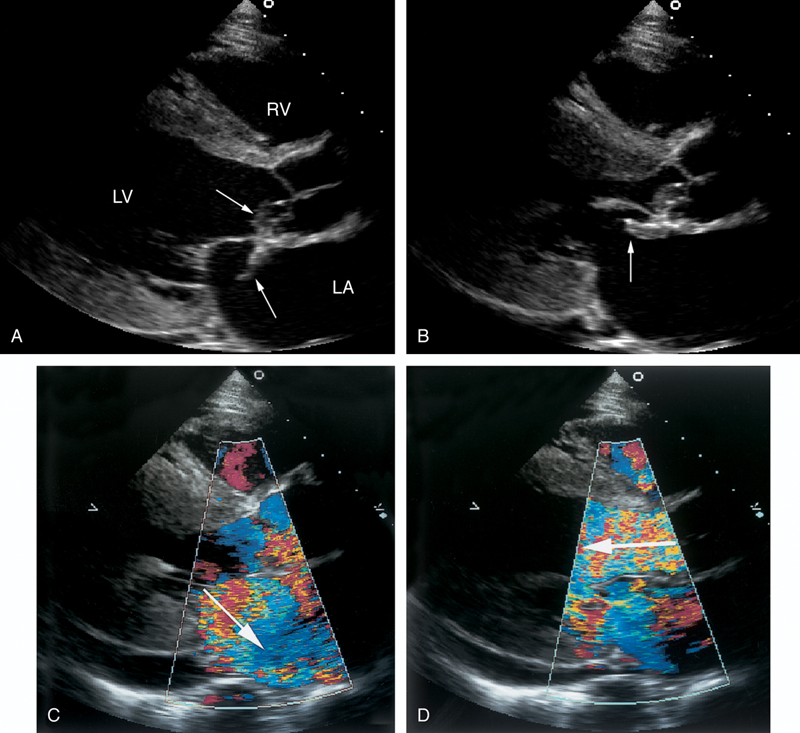

فحوصات تشخيصية لبعض امراض القلب والشرايين التاجية